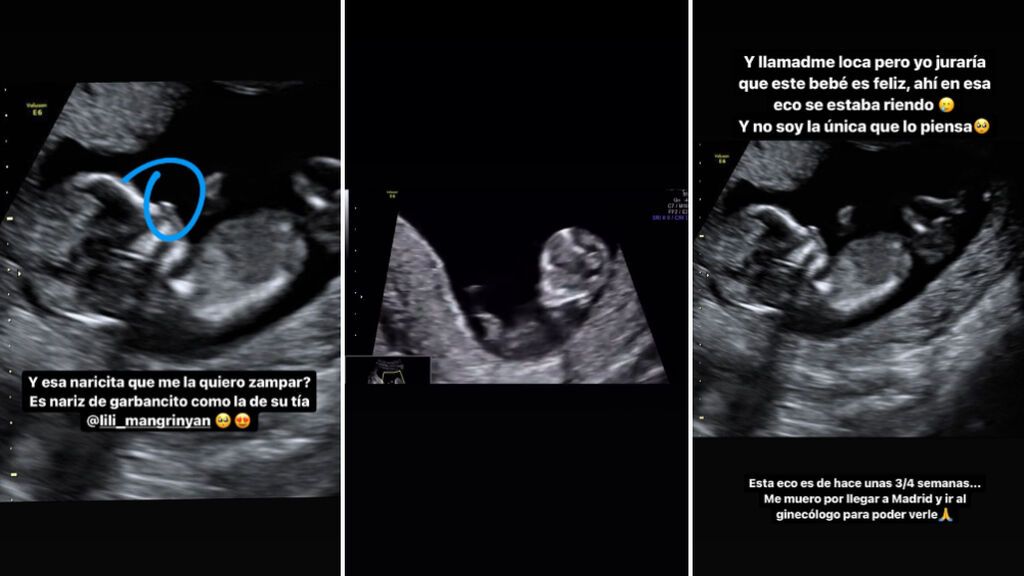

"Por fin podemos contaros que en cinco meses seremos uno o una más. No podemos explicaros con palabras la vorágine de sentimientos y momentos tan bonitos e intensos que hemos estado viviendo estos meses atrás", han declarado junto a unas imágenes en las que se puede ver desde el test de embarazo, positivo, la reacción de su hermana Lila llorando hasta las primeras ecografías del bebé que está en camino.

Es por ello que la propia Violeta ha compartido las aplicaciones a las que ahora está enganchada y que le dicen, según su semana de gestación, qué tamaño tiene ahora su bebé. "Mi bebé es un aguacate o un pollito pekinés", ha explicado divertida. También ha sacado un parecido ya en función de la ecografía. Según la exconcursante de 'Supervivientes' su pequeño tiene la nariz de su hermana.